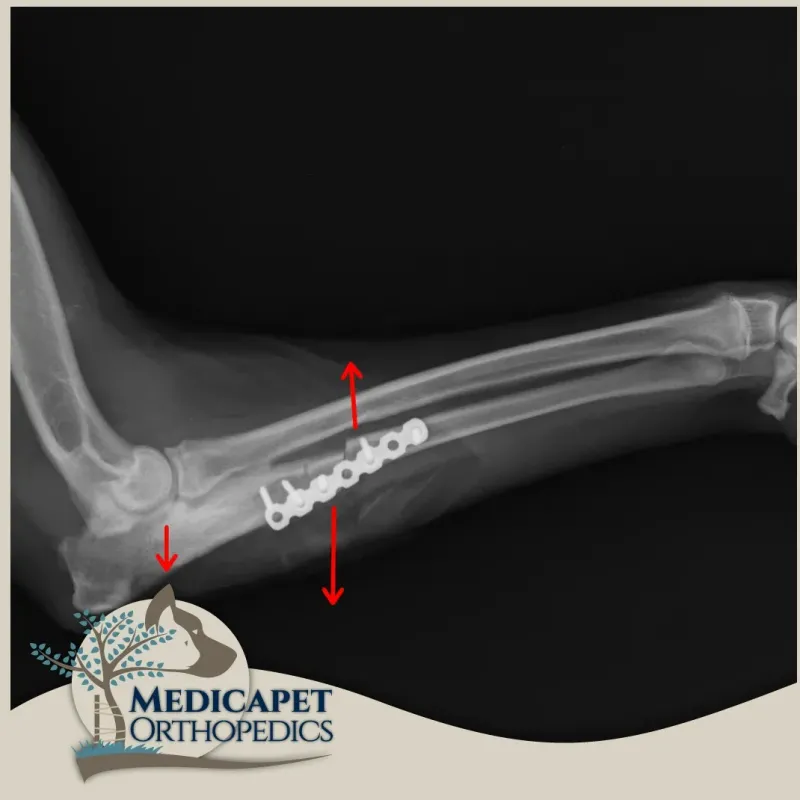

Tedavide cerrahi seçeneklerimizi değerlendiriyoruz. Cerrahi tekniğimize karar verirken displazinin türüne göre hareket etmemiz gerekiyor. Amaç eklemin herhangi bir yerindeki aşırı yükü hafifletmek ya da kaldırmak olduğu için cerrahi tedavi genellikle radius ve ulna kemiklerinde bir takım açısal değişiklikler yapmayı gerektiriyor.

Dirsek displazisi tanısı zor, tedavisi ise profesyonel tekniklere dayanan bir hastalıktır. Bu teknikler milimetrik hassas ölçümlerle uygulamanması gereken tekniklerdir. Bu sebeple sıklıkla BT ya da MRG gibi görüntüleme tekniklerinden faydalanmayı gerektirir.